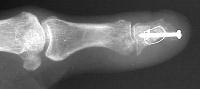

Exploration revealed no discrete  tumor, and a nondiagnostic frozen section. Because of diagnostic uncertainty and in order to avoid intraoperative cross contamination, a cancellous freeze dried allograft was used as a terminal graft:

Click for larger image